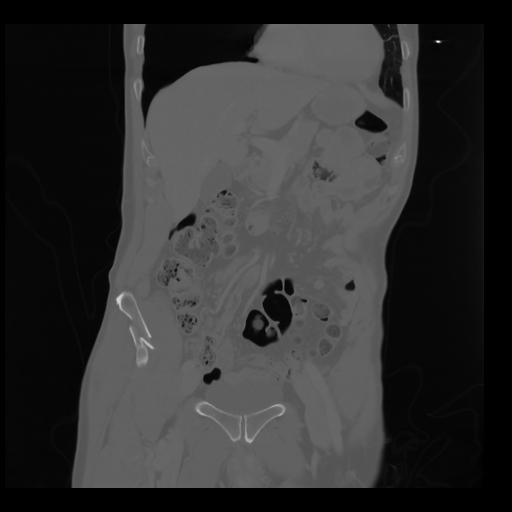

35 CUERPO,CE,Coronal,3.000,CUERPO,Coronal,